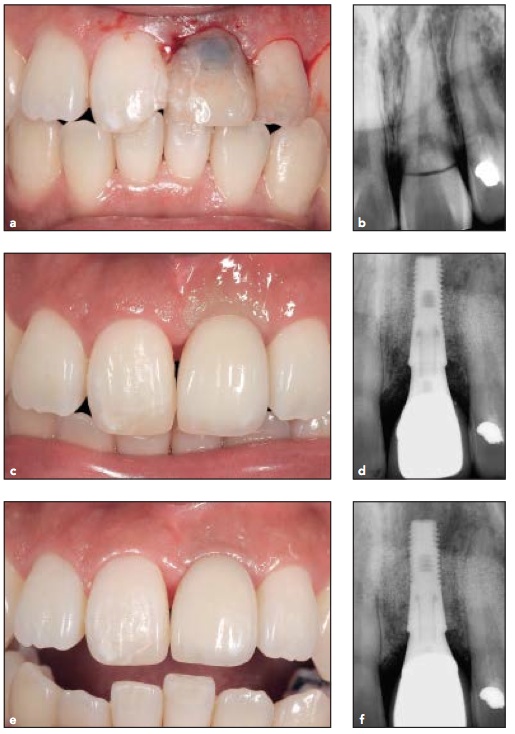

到底在上顎前牙的即拔即種再加上立即負載, 真的可行嗎?這個日本的團隊在18位單顆上顎前牙即拔即種的case(共21支植體), 得到了100%的植體存活率, 而且還去測PES和WES score, 在美觀上也得到很好的評價.

至於治療方法, 我只能說大同小異. 不翻瓣拔牙, 鎖35Ncm, 印模做臨時假牙然後隔一天再loading, 過3個月就做正式假牙. 所以到底要怎麼樣才會成功?Slightly out of contact? 還是因為Astra tech osseospeed厲害?我覺得是他們選case選的好再加上手術醫師的手藝…